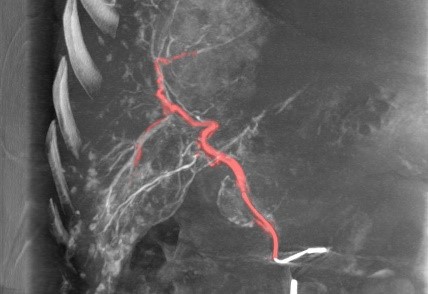

Програмне забезпечення 3D Roadmap

Флюороскопія в реальному масштабі часу накладається на об’ємні 3D зображення, що були отримані під час 3D ангіографії. При русі столу під час роботи в режимі 3D Roadmap автоматично відбувається співставлення зображення 3D та флюороскопічного. Всі рухи системи пов’язані з накладанням 3D об’єму та скопічних зображень, включаючи зміну кута нахилу С-арки, SID, розміру поля огляду, висоти позиціонування столу. Можливим є зсув попіксельно вручну для більш точного співставлення об’єму та флюоро.